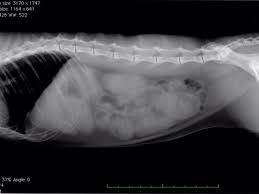

次に紹介するのは、猫のおもちゃを誤って飲み込んでしまった犬のレントゲン写真です。お腹の中に猫のおもちゃがはっきりと写っているこの写真は、シュールでありながらも、飼い主にとっては重大な問題を示しています。

幸いにも、この犬は無事におもちゃを取り出すことができたそうです。